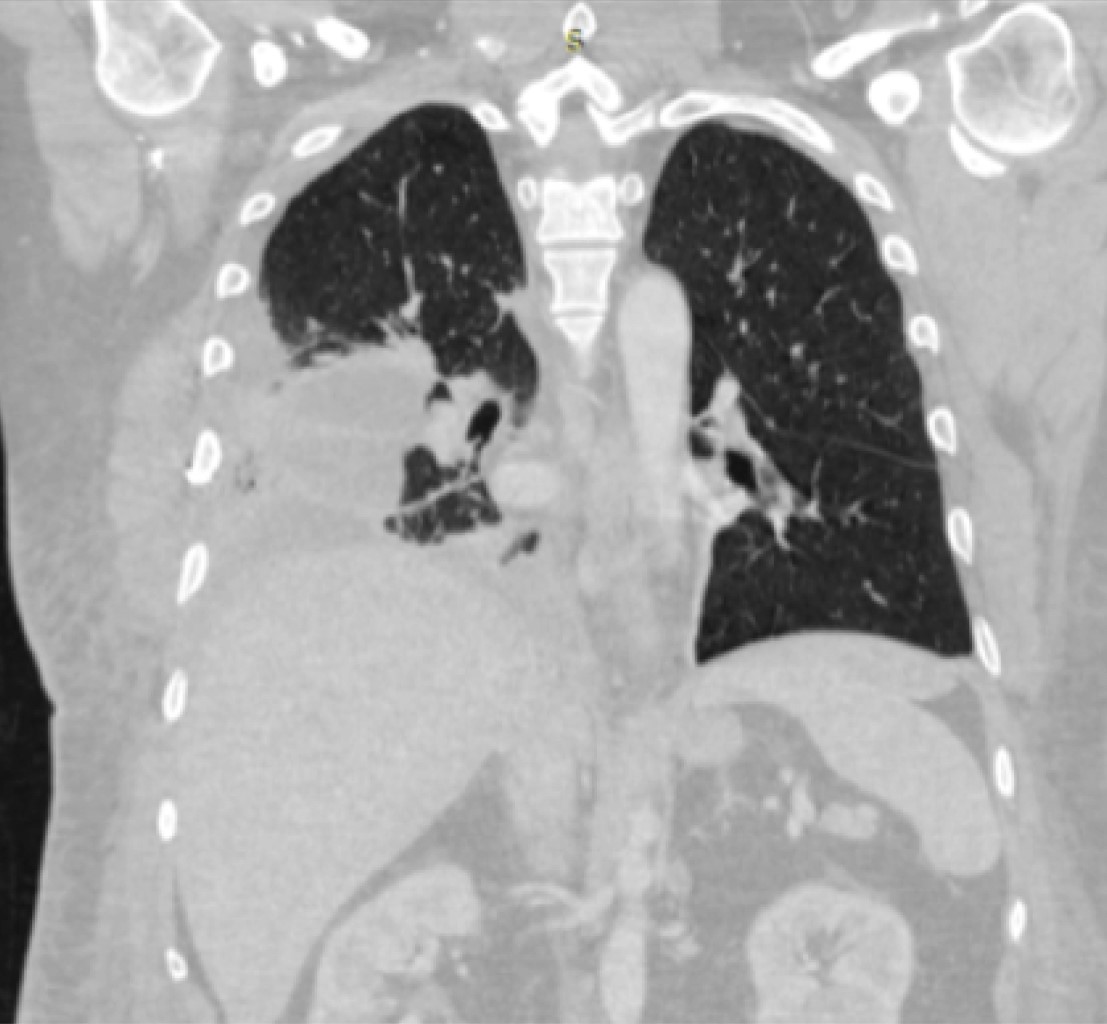

Estudios de laboratorio normales, exceptuando leucocitos: 14.2 mil/mm³, CPK 2,948 μmol/L. Se realiza radiografía de tórax (Figura 1) y tomografía computarizada (TC) toraco-abdominal (Figura 2, 3 y 4) observando neumotórax derecho de 30%, fracturas costales bilaterales de segunda a la séptima. En ambos estudios no se evidencia la presencia de hernia diafragmática.

En el paciente traumatizado que se encuentra estable, la TC con contraste intravenoso es el estudio de referencia para el diagnóstico y planeación quirúrgica, con una sensibilidad de 14-71% y especificidad de 76-99%2, y aumenta si se utiliza la TC helicoidal con reconstrucción en 3D (sensibilidad 82-87%, especificidad 72-99%).8 Magu y colaboradores reportan una sensibilidad similar a la radiografía de tórax hasta en 50%.5 Los datos tomográficos más sugestivos se muestran en la Tabla 1.2,8

Figura 3